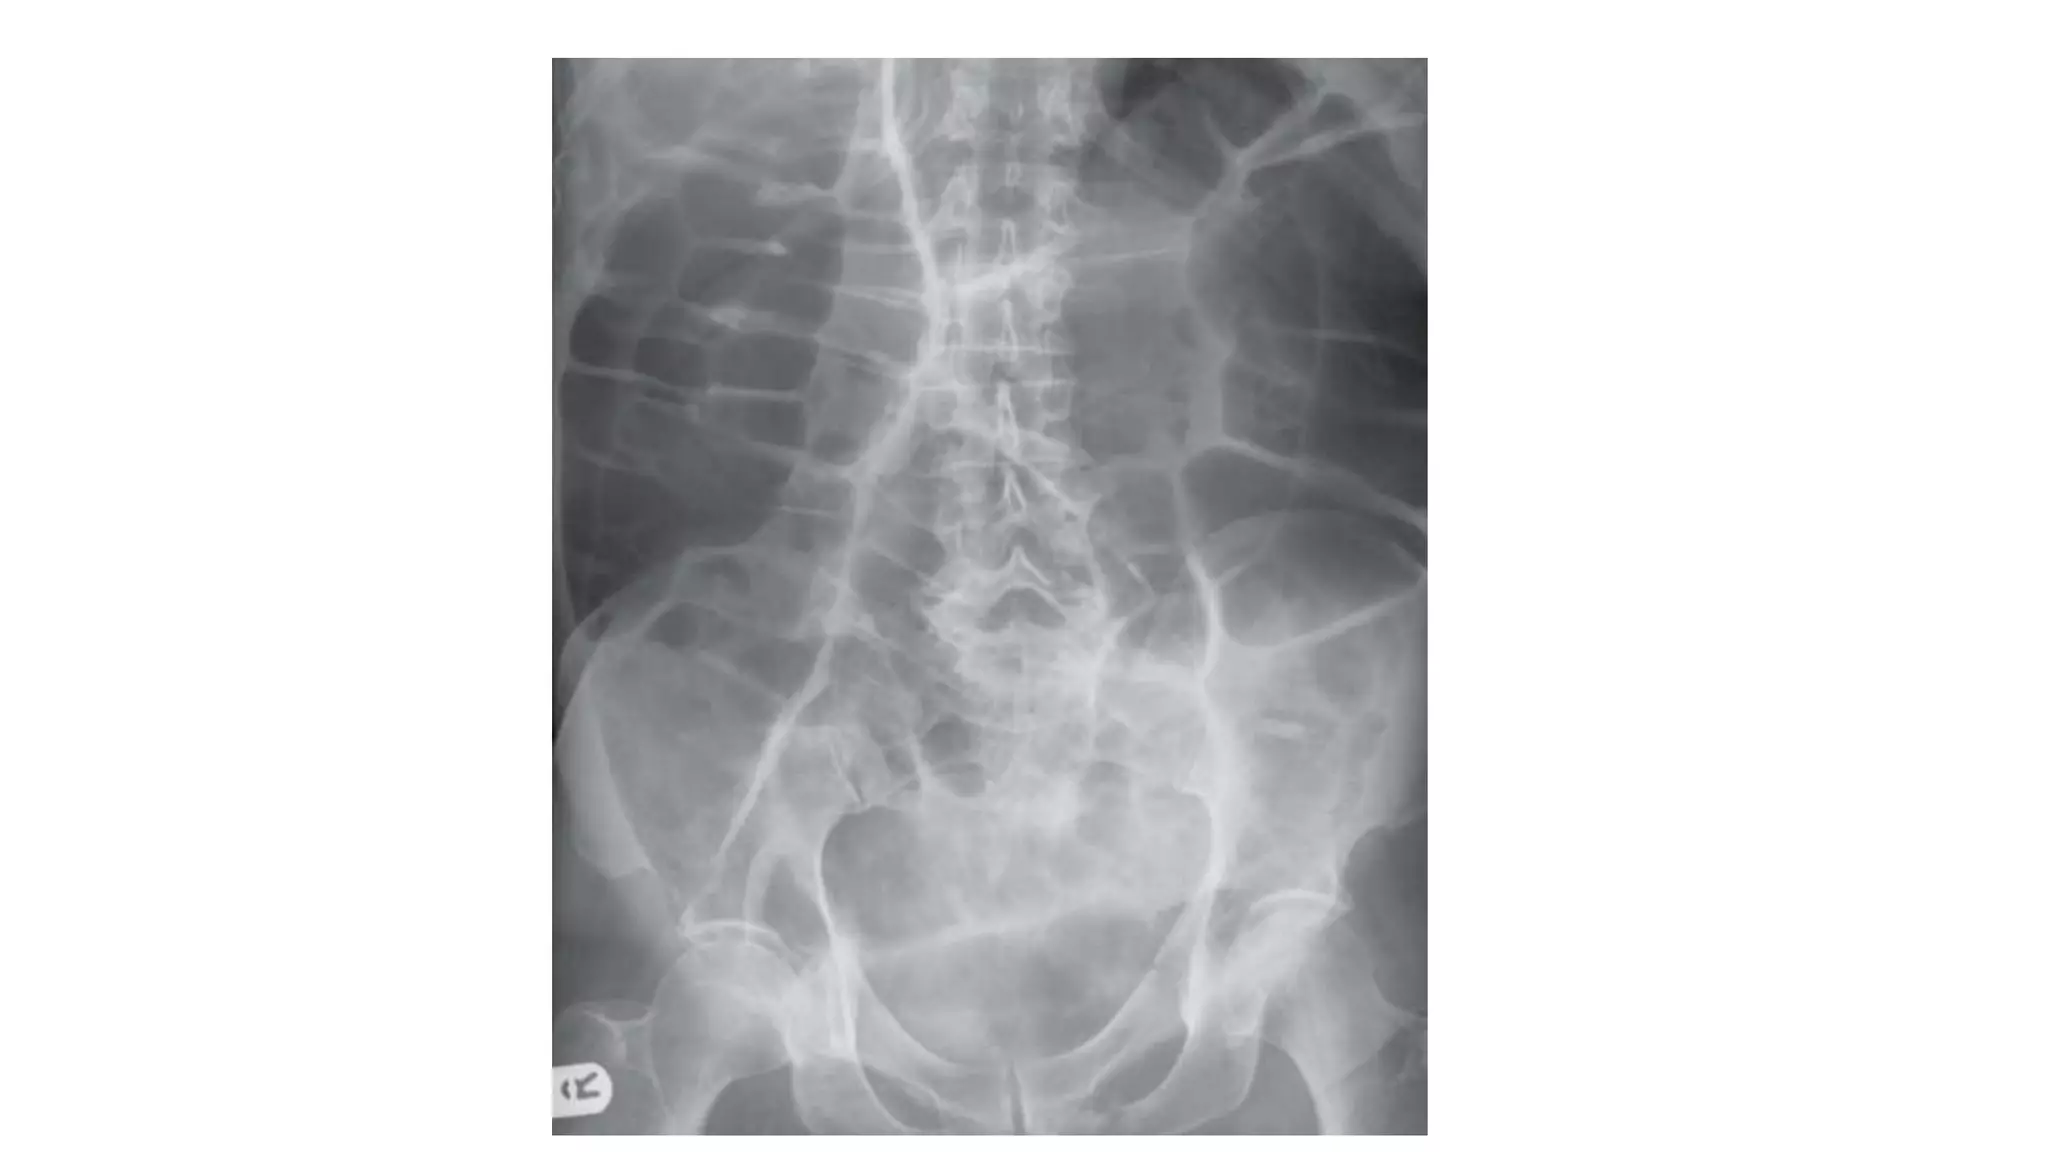

Radiological signs to look for:

• Dilation >3 cm: The small bowel is dilated if it measures over 3 cm in

diameter.

• Central location: The dilated loops are more likely to be centrally

located on the abdominal radiograph.

• Valvulae conniventes: These are the mucosal folds of the small

intestine. They are thin, closely spaced and classically seen as a

continuous thin line across the entire width of the bowel.

• Air fluid level in upright position

Who wants to be a hero ?

Pick up 3 findings